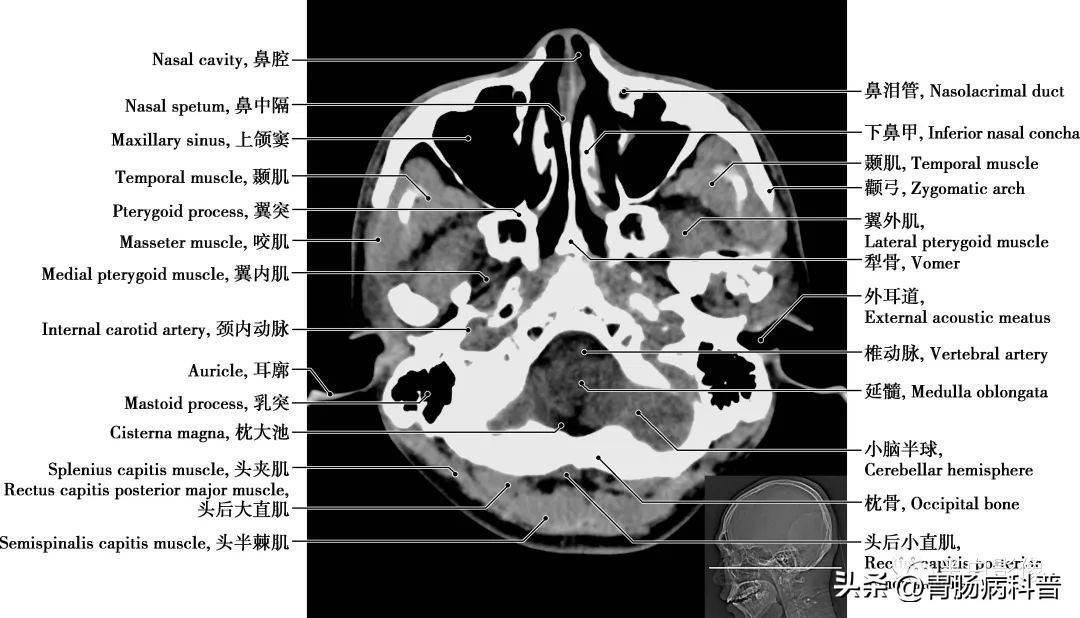

图1-1-19 经小脑扁桃体轴位切面

上颌窦 为上颌骨体内的锥形空腔,位于上颌骨体内,窦壁为骨质,覆黏膜,向内侧开口于中鼻道,分为一底、一尖及前、后、上、下四个壁。由于窦口高于窦底部,故在直立位时若有炎性物不易自然流出。外耳道 为外耳门至鼓膜的管道,呈弯曲状,由外向内,先向前上,继而稍向后,弯向前下